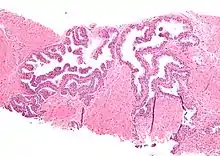

| Micrograph showing high-grade prostatic intraepithelial neoplasia. H&E stain. | |

Microscopically, PIN is a collection of irregular, atypical epithelial cells. The architecture of the glands and ducts remains normal. The epithelial cells proliferate and crowding results in a pseudo-multilayer appearance. They remain fully contained within a prostate acinus (the berry-shaped termination of a gland, where the secretion is produced) or duct. The latter can be demonstrated with special staining techniques (immunohistochemistry for cytokeratins) to identify the basal cells forming the supporting layer of the acinus. In prostate cancer, the abnormal cells spread beyond the boundaries of the acinus and form clusters without basal cells. In HGPIN, the basal cell layer is disrupted but present. PIN is primarily found in the peripheral zone of the prostate (75-80%), rarely in the transition zone (10-15%) and very rarely in the central zone (5%), a distribution that parallels the zonal distribution for prostate carcinoma.[7]

Several architectural variants of PIN have been described, and many cases have multiple patterns. The main ones are tufting, micropapillary, cribriform, and flat. Although these different appearances may cause confusion with other conditions, they have not been found to be of clinical importance. Rarer types are signet-ring-cell, small-cell-neuroendocrine, mucinous, foamy, inverted, and with squamous differentiation.[3]